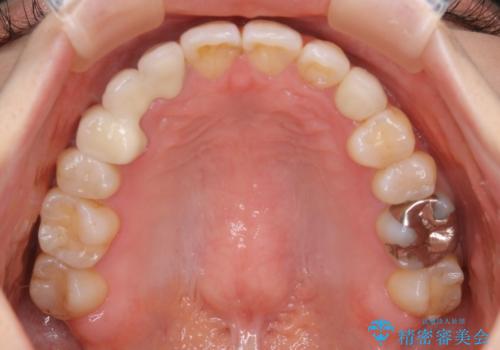

- 受け口で、前歯の嚙み合わせが気になるとの事でご相談にいらした方です。先天的に右上犬歯がなく、左上犬歯も小さい状態でした。矯正治療にて周囲の歯を動かして歯のスペースを確保した上で、被せものにて歯を作っていきました。

歯科技工士さんの熟練した技術により、周囲の歯としっかりなじむ天然歯のような被せ物をお作りすることが出来ました。

矯正治療と補綴治療をうまく組み合わせることで、美しい口元に仕上げることが出来ました。矯正治療、補綴治療をまとめて行える総合歯科治療を体現した治療といえます。